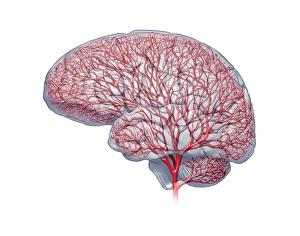

The central nervous system, the intricate network that governs our every thought and movement, is a marvel of complexity. From the delicate cerebellum tissue to the detailed light micrograph capturing its essence, we are reminded of its importance in maintaining balance and coordination. Anatomy comes alive as we explore the human brain from an inferior view. The intricacy of brain fibers is revealed through DTI MRI scans like C017/7099 and C017/7035, showcasing their vital role in transmitting information throughout this extraordinary organ. Artistic renderings bring us closer to understanding the medulla oblongata's significance within the brain. Its portrayal in various artworks allows us to appreciate how it controls essential functions such as breathing and heart rate. As we delve deeper into studying the central nervous system, models of the human brain provide invaluable insights into its structure and organization. Lateral views reveal countless regions responsible for cognition, emotion regulation, sensory perception, and motor control. Microscope slides offer glimpses into nerve cells' intricate architecture—a testament to their ability to transmit electrical signals at lightning speed. Meanwhile, glial stem cell cultures captured under a light microscope remind us of their crucial role in supporting neuronal function. Finally, artistic representations unveil the limbic system's enigmatic nature—an interconnected web responsible for emotions and memory formation. These captivating artworks allow us to visualize this complex network within our brains. Exploring these hints provides a glimpse into the awe-inspiring world of our central nervous system—the very foundation upon which our thoughts, actions, memories reside—reminding us just how remarkable our brains truly are.